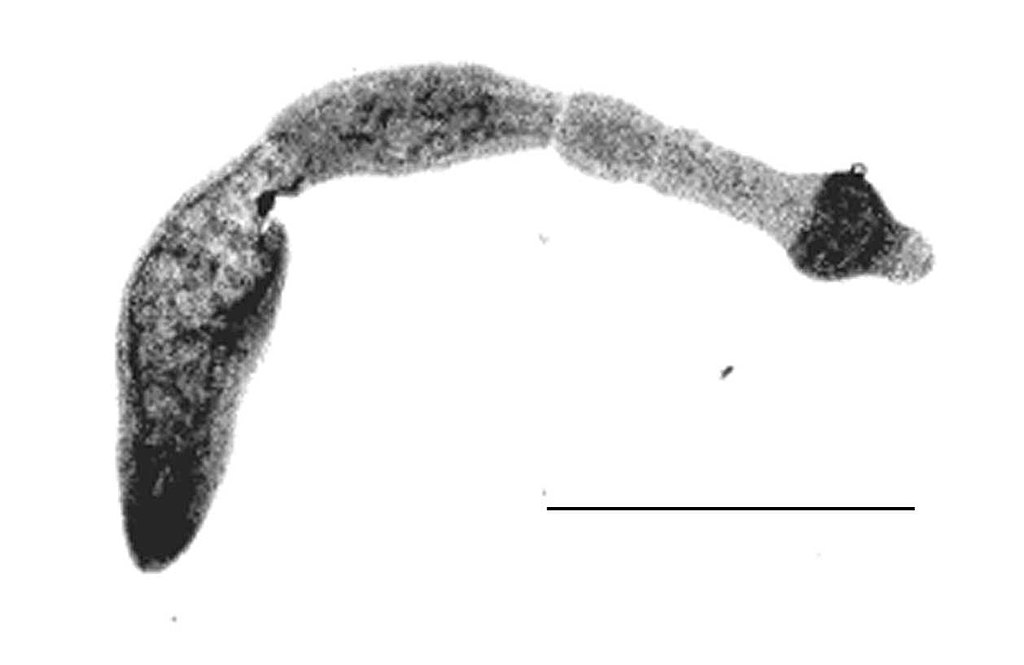

Credits Echinococcus multilocularis, der Fuchsbandwurm. Grafik: , Echinococcus multilocularis, als gemeinfrei gekennzeichnet, Details auf Wikimedia Commons↩︎